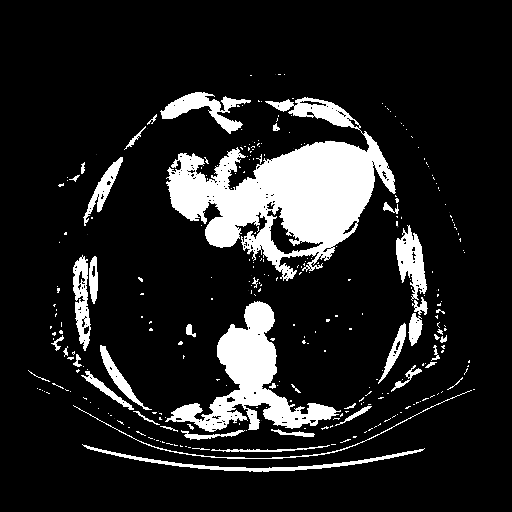

Original VENOUS CT scan

Full window (WL 1023.5, WW 4095 β†’ Low βˆ’1024, High +3071)

Actual HU range: [-1024.0, 3071.0]